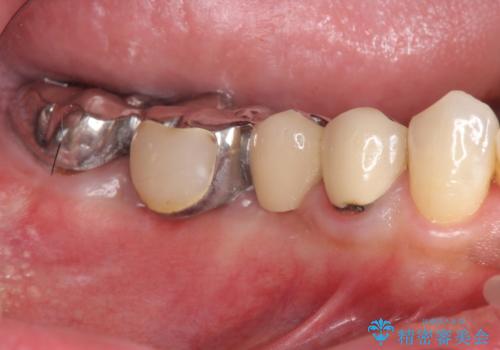

[歯の破折] インプラント埋入を行うための大規模骨造成